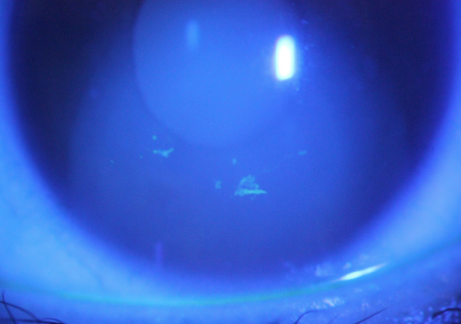

2. Corneal pathogen infection can also lead to epithelial lesions. The most common is corneal epithelial lesions caused by herpes simplex virus. The virus activates and replicates in epithelial cells, causing epithelial cell necrosis and disintegration, and then epithelial abscission. The typical herpes simplex virus corneal ulcer is dendritic, terminal bifurcation and nodular enlargement.

Figure 3. Dendritic ulcer of corneal epithelium caused by herpes simplex virus